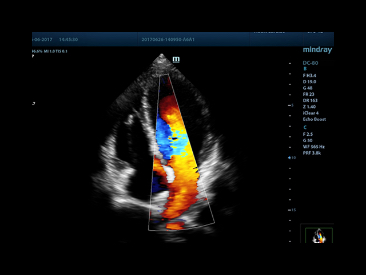

Auto EF

One intelligent way to analyze 2D echo clips to automatically recognize diastole/systole frames and output EDV/ESV/EF etc. results by Simpson method.